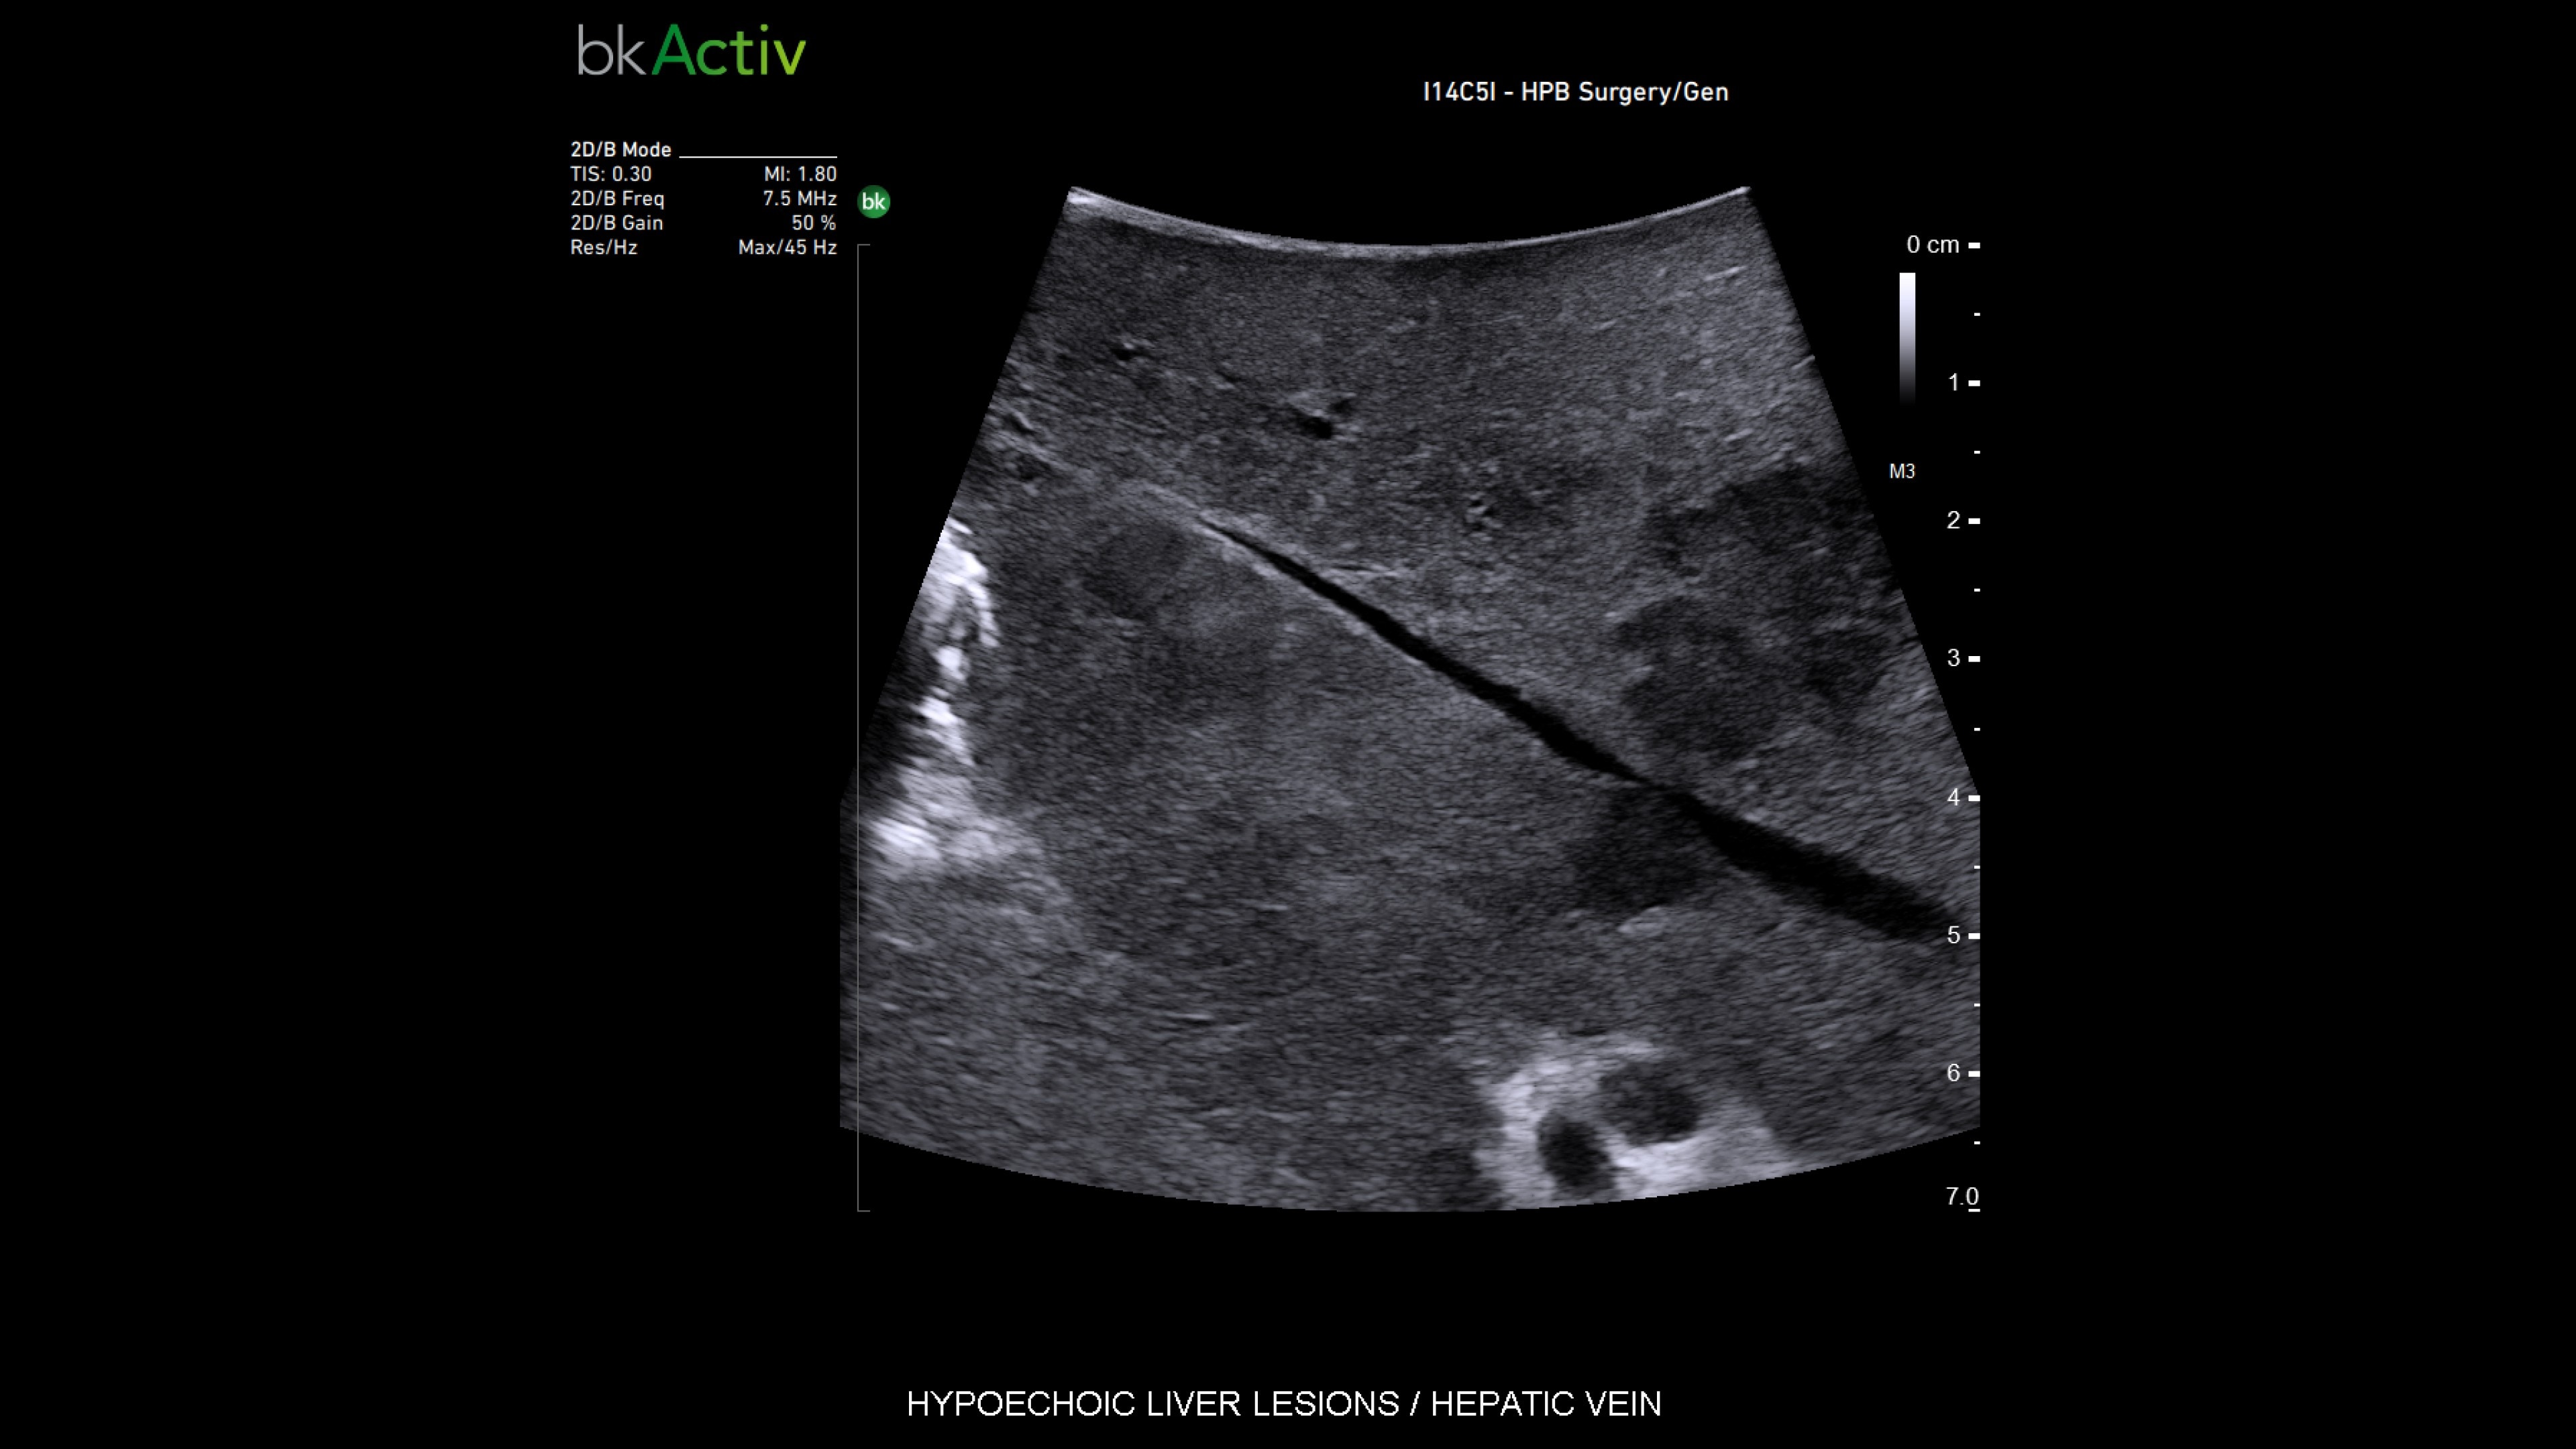

Resection ultrasound

Active imaging supports liver and pancreas tumor resection procedures by helping you visualize complex anatomical variations and relationships to vascular structures, identify tumor location, define adequate margins of resection, and assess surgical planning.

Active imaging with intraoperative ultrasound supports critical decision-making in open or minimally invasive tumor resections.

• Visualize complex anatomical variations.

• Identify tumor location, proximity, and invasion of vasculature.

• Define adequate margins of resection.

• Understand relationship to vascular structures.

• Assess surgical planning and check for vessel patency at the end of the procedure.